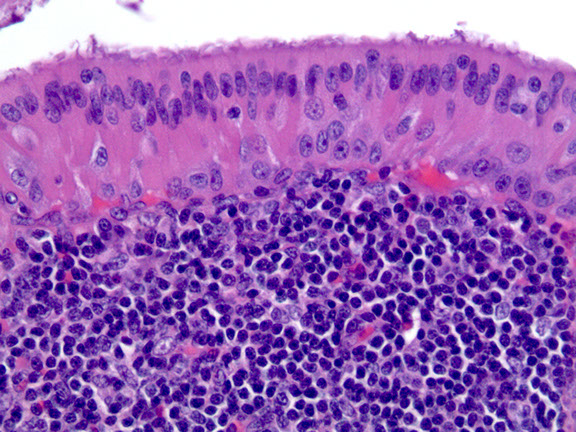

Micro: Reactive epithelial cells ("epithelial-myoepithelial islands") surrounded by heavy inflam

- these epithelial cells are ectopic tissue possibly derived from the branchial pouch

Lymphoepithelial cyst

Subacute necrotizing sialadenitis of the left palate c focal acinar necrosis (stars)